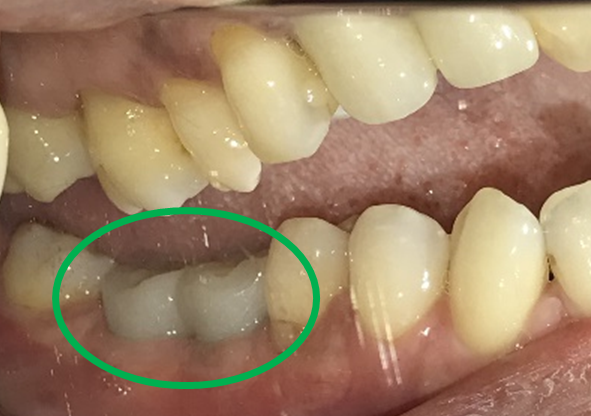

左下の抜けているところに歯を入れたい。

治療内容

インプラントを2本埋入しました。

所感

以前、1本歯がないところを、欠損の両側に被せ物をしてつないだブリッジでした。その2本のうちの前方の歯が歯根の破折を起こし、抜歯になり2本の欠損になりました。この2本の欠損を補う方法には、部分入れ歯、再度ブリッジ、インプラントの3つの方法があります。部分入れ歯もブリッジも欠損部分の負担をほかの歯に負わせるため、支台になった歯は負担が大きくなり、虫歯、歯周病、歯根破折の危険性が高まり、さらに歯を失うことになります。インプラントは、それ自身が単体で植立しているため他の歯に負担を負わすことがありませんので、咬合を回復させるだけではなく、他の歯を守る役割もあります。今回もX-Guideを使った埋入で、安心安全に行うことできました。

インプラント2本:¥363,000×2本=¥726,000(税込)

Before

After